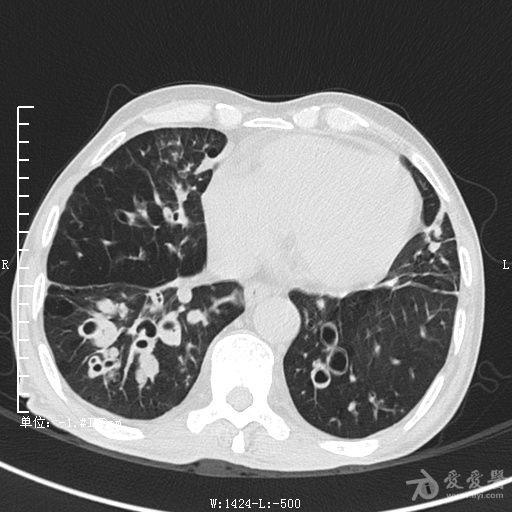

典型支气管扩张及肺水肿CT片

典型支气管扩张肺水肿